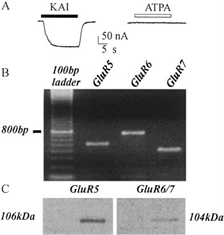

Espressione dei Recettori Neurotrasmettitoriali Umani del Lobo Temporale Epilettico in Oociti di Xenopus: un Approccio Innovativo per lo Studio dell’Epilessia

Lo studio introduce un modello innovativo per lo studio dell’epilessia, dimostrando come recettori neuronali del lobo temporale umano espressi in oociti di Xenopus mostrino alterazioni funzionali che contribuiscono all’eccitabilità cerebrale tipica dell’epilessia farmacoresistente.